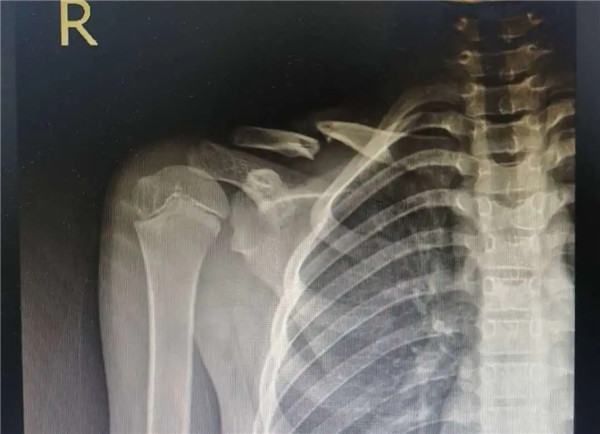

復(fù)位前

經(jīng)拍片顯示,洋洋右鎖骨中遠(yuǎn)段骨折。查體時(shí),洋洋右肩部腫脹,有壓痛感,右肩關(guān)節(jié)上舉、外展活動(dòng)受限,建議其入院并接受手術(shù)治療。洋洋媽媽當(dāng)即辦理了入院手續(xù)。

6月3日,在征得家屬同意,洋洋的身體符合手術(shù)指征后,洋洋接受了右鎖骨骨折切開復(fù)位內(nèi)固定術(shù),手術(shù)由應(yīng)文世主任主刀。術(shù)中可見右鎖骨呈粉碎性骨折,骨折端移位明顯。一個(gè)小時(shí)后,手術(shù)順利結(jié)束。術(shù)后,洋洋恢復(fù)良好,6月9日順利出院。一個(gè)月后,在來復(fù)查時(shí),洋洋的媽媽帶來了一面錦旗送予應(yīng)文世主任及手外科周小君副主任,以感謝他們的高超技術(shù)及優(yōu)質(zhì)服務(wù)。

復(fù)位后